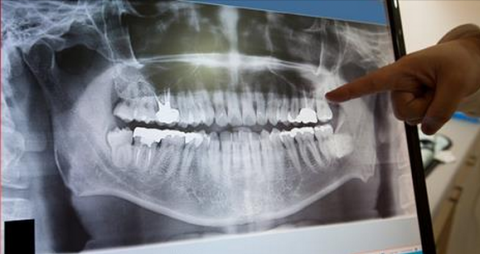

Dental X-Rays Are Safe

One of the most common things done at a routine dental visit is having x-rays. It’s those x-rays that allow the dentist to take a closer look at the overall health of your teeth to detect damage and disease affecting the roots and bones of your mouth, and to look for any possible cavities – things that aren’t visible during a routine visual exam. Sounds good, right? But then we cover you in a heavy vest and ask pregnant women to forgo x-rays which prompts lots of questions from our patients about dental x-ray safety. So, let’s talk about it!